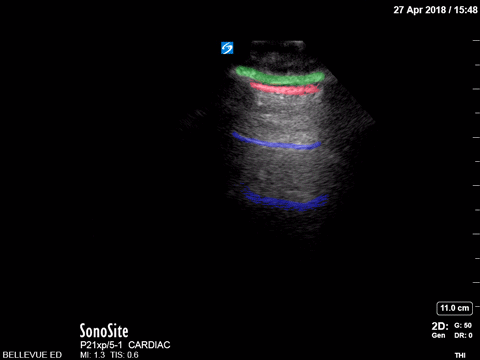

Pulmonary - Lung Sliding - Colorized

Lung sliding Green: Subcutaneous tissue, Red: Pleural space, Blue: A lines Images: Dr. Lindsay Davis, Dr. Hannah Kopinski. Image Editing: Michael Amador and Dr. Matthew Riscinti